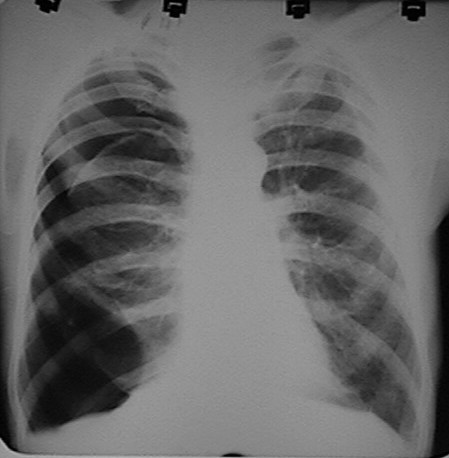

Click Imagen Ampliada

Fig.  Femenina. 70 años.  APP: mastectomía derecha. MC: dolor torácico derecho. Se diagnóstica derrame pleural. RX realizada post-toracocentesis. Gran NHA en la región central del hemitórax derecho en relación con hemo-neumotórax.